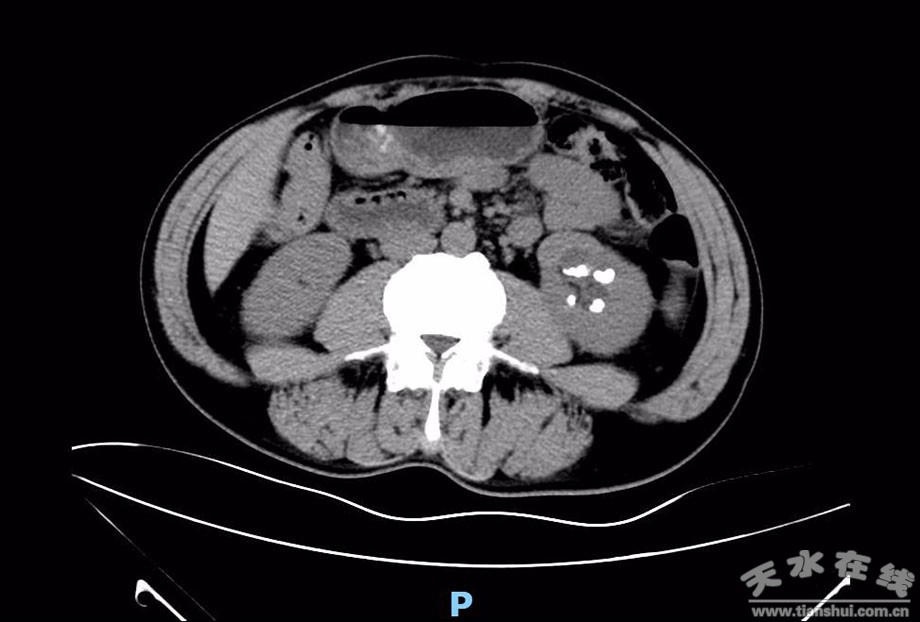

經(jīng)了解患者蘇先生因左側(cè)腰部脹痛不適2年,以“ 左腎積水伴輸尿管結(jié)石、左腎結(jié)石”收治住市一院;颊咭蜃髠(cè)輸尿管多發(fā)結(jié)石造成左側(cè)上尿路梗阻,左腎中度積水,腎功能受損,合并左腎內(nèi)多發(fā)結(jié)石。經(jīng)過(guò)市一院醫(yī)生精心手術(shù)治療,解除了困擾患者兩年多的病痛,市一院醫(yī)護(hù)不僅在患者住院期間精心治療,還在出院時(shí)為患者做了詳細(xì)的健康宣教,告訴患者預(yù)防減少結(jié)石復(fù)發(fā)的方法,讓患者受益匪淺。患者感激之情溢于言表,復(fù)診時(shí)帶著寫(xiě)好的感謝信,表達(dá)了對(duì)市一院醫(yī)護(hù)人員的感激與信任。

(術(shù)前多發(fā)左腎結(jié)石)

(術(shù)后結(jié)石完全清除并留置輸尿管支架)